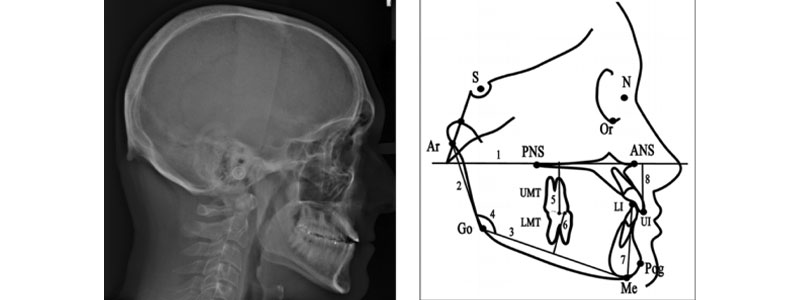

Ramus height and the gonial angle are key elements in the determination of skeletal facial types. An acute gonial angle is associated with a flat mandibular plane and a brachy-facial type individual. Alternatively, the dolichofacial type individual has an obtuse gonial angle and a steeper mandibular plane angle.

Lateral growth patterns are commonly known as Angles-type growth patterns: Angles Class-I, Class II, and Class III. These class types are based upon molar and cuspid relationships relative to mandibular length. These classifications and terminologies involve complex growth and development details.

The VDO is the result of musculoskeletal balance during growth. The bottom line is that the patient’s VDO is directly related to mandibular length and height. Cephalometric analysis does not give the ideal value of the vertical dimension, but the skeletal pattern can provide direction as to the predictability of opening or closing the OVD.